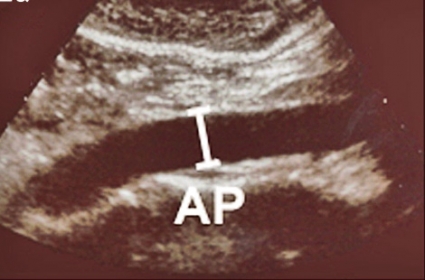

Ultraljudsundersökningen vid screening (Figur 2) skiljer sig från en fullvärdig aortaundersökning såtillvida att dess primära syfte är att med hög säkerhet utesluta sjukdom. Vid screening läggs transduktorn i kärlets längsriktning (Figur 2 a) och maximal infrarenal anteroposterior diameter mäts enligt principen »leading edge to leading edge« (Figur 3). Måttet anges på ett protokoll, som också innehåller uppgifter om eventuella visibilitetsproblem samt undersökarens initialer. Vid diameter ≥25 mm anges också diametern med transduktorn vinkelrätt mot kärlet (Figur 2 b).